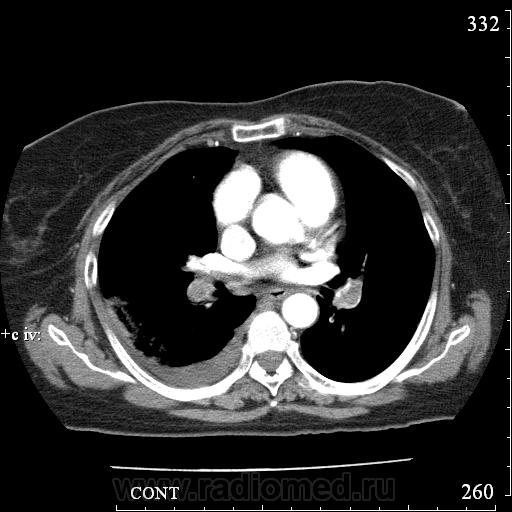

Еще один случай диагностики ТЭЛА методом КТ-ангиографии у женщины 59 лет. Основная клиническая жалоба - выраженная одышка. Определяется: полный дефект наполнения в системе правой ЛА (бифукация и нижнедолевая), неполный дефект наполнения в левой ЛА (нижнедолевая), пристеночные тромбы по задней стенке в области бифуркации обеих легочных артерий. Инфаркт (массивное кровоизлияние) нижней доли правого легкого. Правосторонний малый (120см3) гидроторакс. Несмотря на выраженные тромбы, поперечники легочных артерий - в пределах нормы.; на нативной (безконтрастной) КТ - тромбы не видны. Несмотря на почти полный дефект наполнения в левой нижнедолевой артерии, изменений в легочной ткани левого легкого нет. Также приводится топограмма, как вариант, приближенный к рутинной рентгенограмме

В данном случае не просто КТ, КТ-ангиография - сила. Нативное КТ, также не ответило бы на все вопросы.